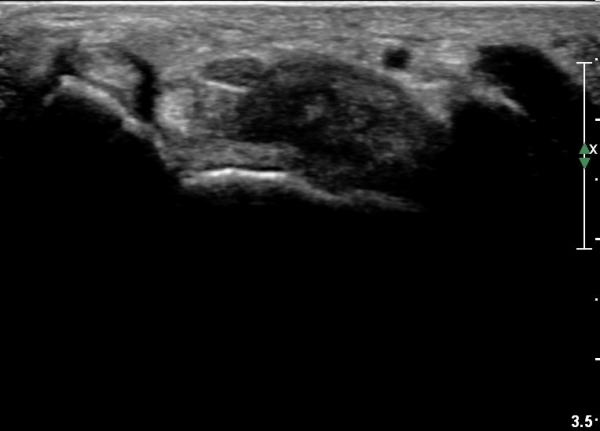

¼ö±Ù°ü ¿øÀ§ºÎ Ⱦ´Ü¸é°Ë»ç¿¡¼­ Á¤Á߽ŰæÀÇ ºÎÁ¾ µî ƯÀÌ ¼Ò°ßÀÌ º¸ÀÌÁö ¾Ê´Â´Ù(»çÁø 3).